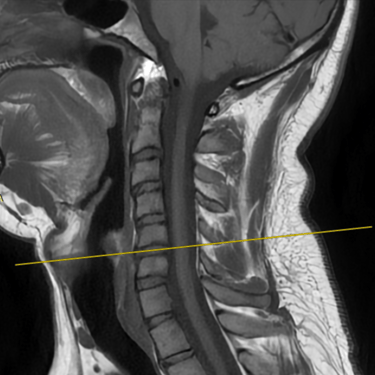

Discopatía Cervical con Inestabilidad de Columna | Diagnóstico por Resonancia Magnética

La discopatía cervical con inestabilidad de columna es una patología que compromete la movilidad y estabilidad de la región cervical, generando síntomas como dolor cervical crónico, rigidez, irradiación a miembros superiores y, en casos avanzados, déficit neurológico. La resonancia magnética (RMN) es el método diagnóstico de elección, ya que permite evaluar la degeneración discal, protrusiones o hernias discales, cambios en los cuerpos vertebrales, compresión radicular y signos de inestabilidad. Su precisión ayuda a planificar el tratamiento más adecuado, que puede incluir manejo conservador o cirugía, según la gravedad y el compromiso neurológico del paciente.